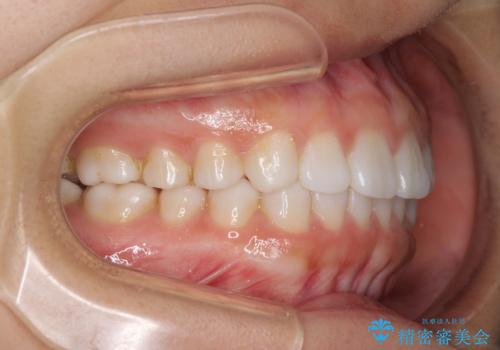

インビザラインによる軽度な出っ歯の矯正治療

- 上の前歯の出っ歯を治したいとのことで来院された患者様です。

上下顎ともにIPR(歯と歯の間を削る)と歯列全体の拡大によって口元が引っ込むように設計し、インビザラインにより治療を行うこととしました。

どこまで口元を引っ込めることができるのか、患者様自身も正直分からない部分があったため、少しずつ治療ゴールを変更しながら仕上げていきました。

気になっていた前歯の飛び出した印象は、最終的にはスッキリと引っ込み、大変満足していただきました。